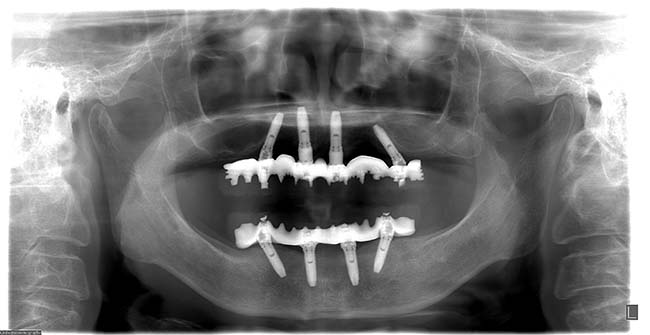

若い歯周病患者(30代)のAll-on-4

| 患者さま情報 | 治療期間 | 治療費 |

|---|---|---|

| 30代 男性 | 1年4ヶ月 | 2,491,000円 |

リスクや副作用

・保険外で高い

・治療が適応とならないケースがある。

・十分なメンテナンスがないと、失敗やトラブルを招く可能性がある。

治療経験・技術がある医師による治療が必要となる。

・外科的治療が必要